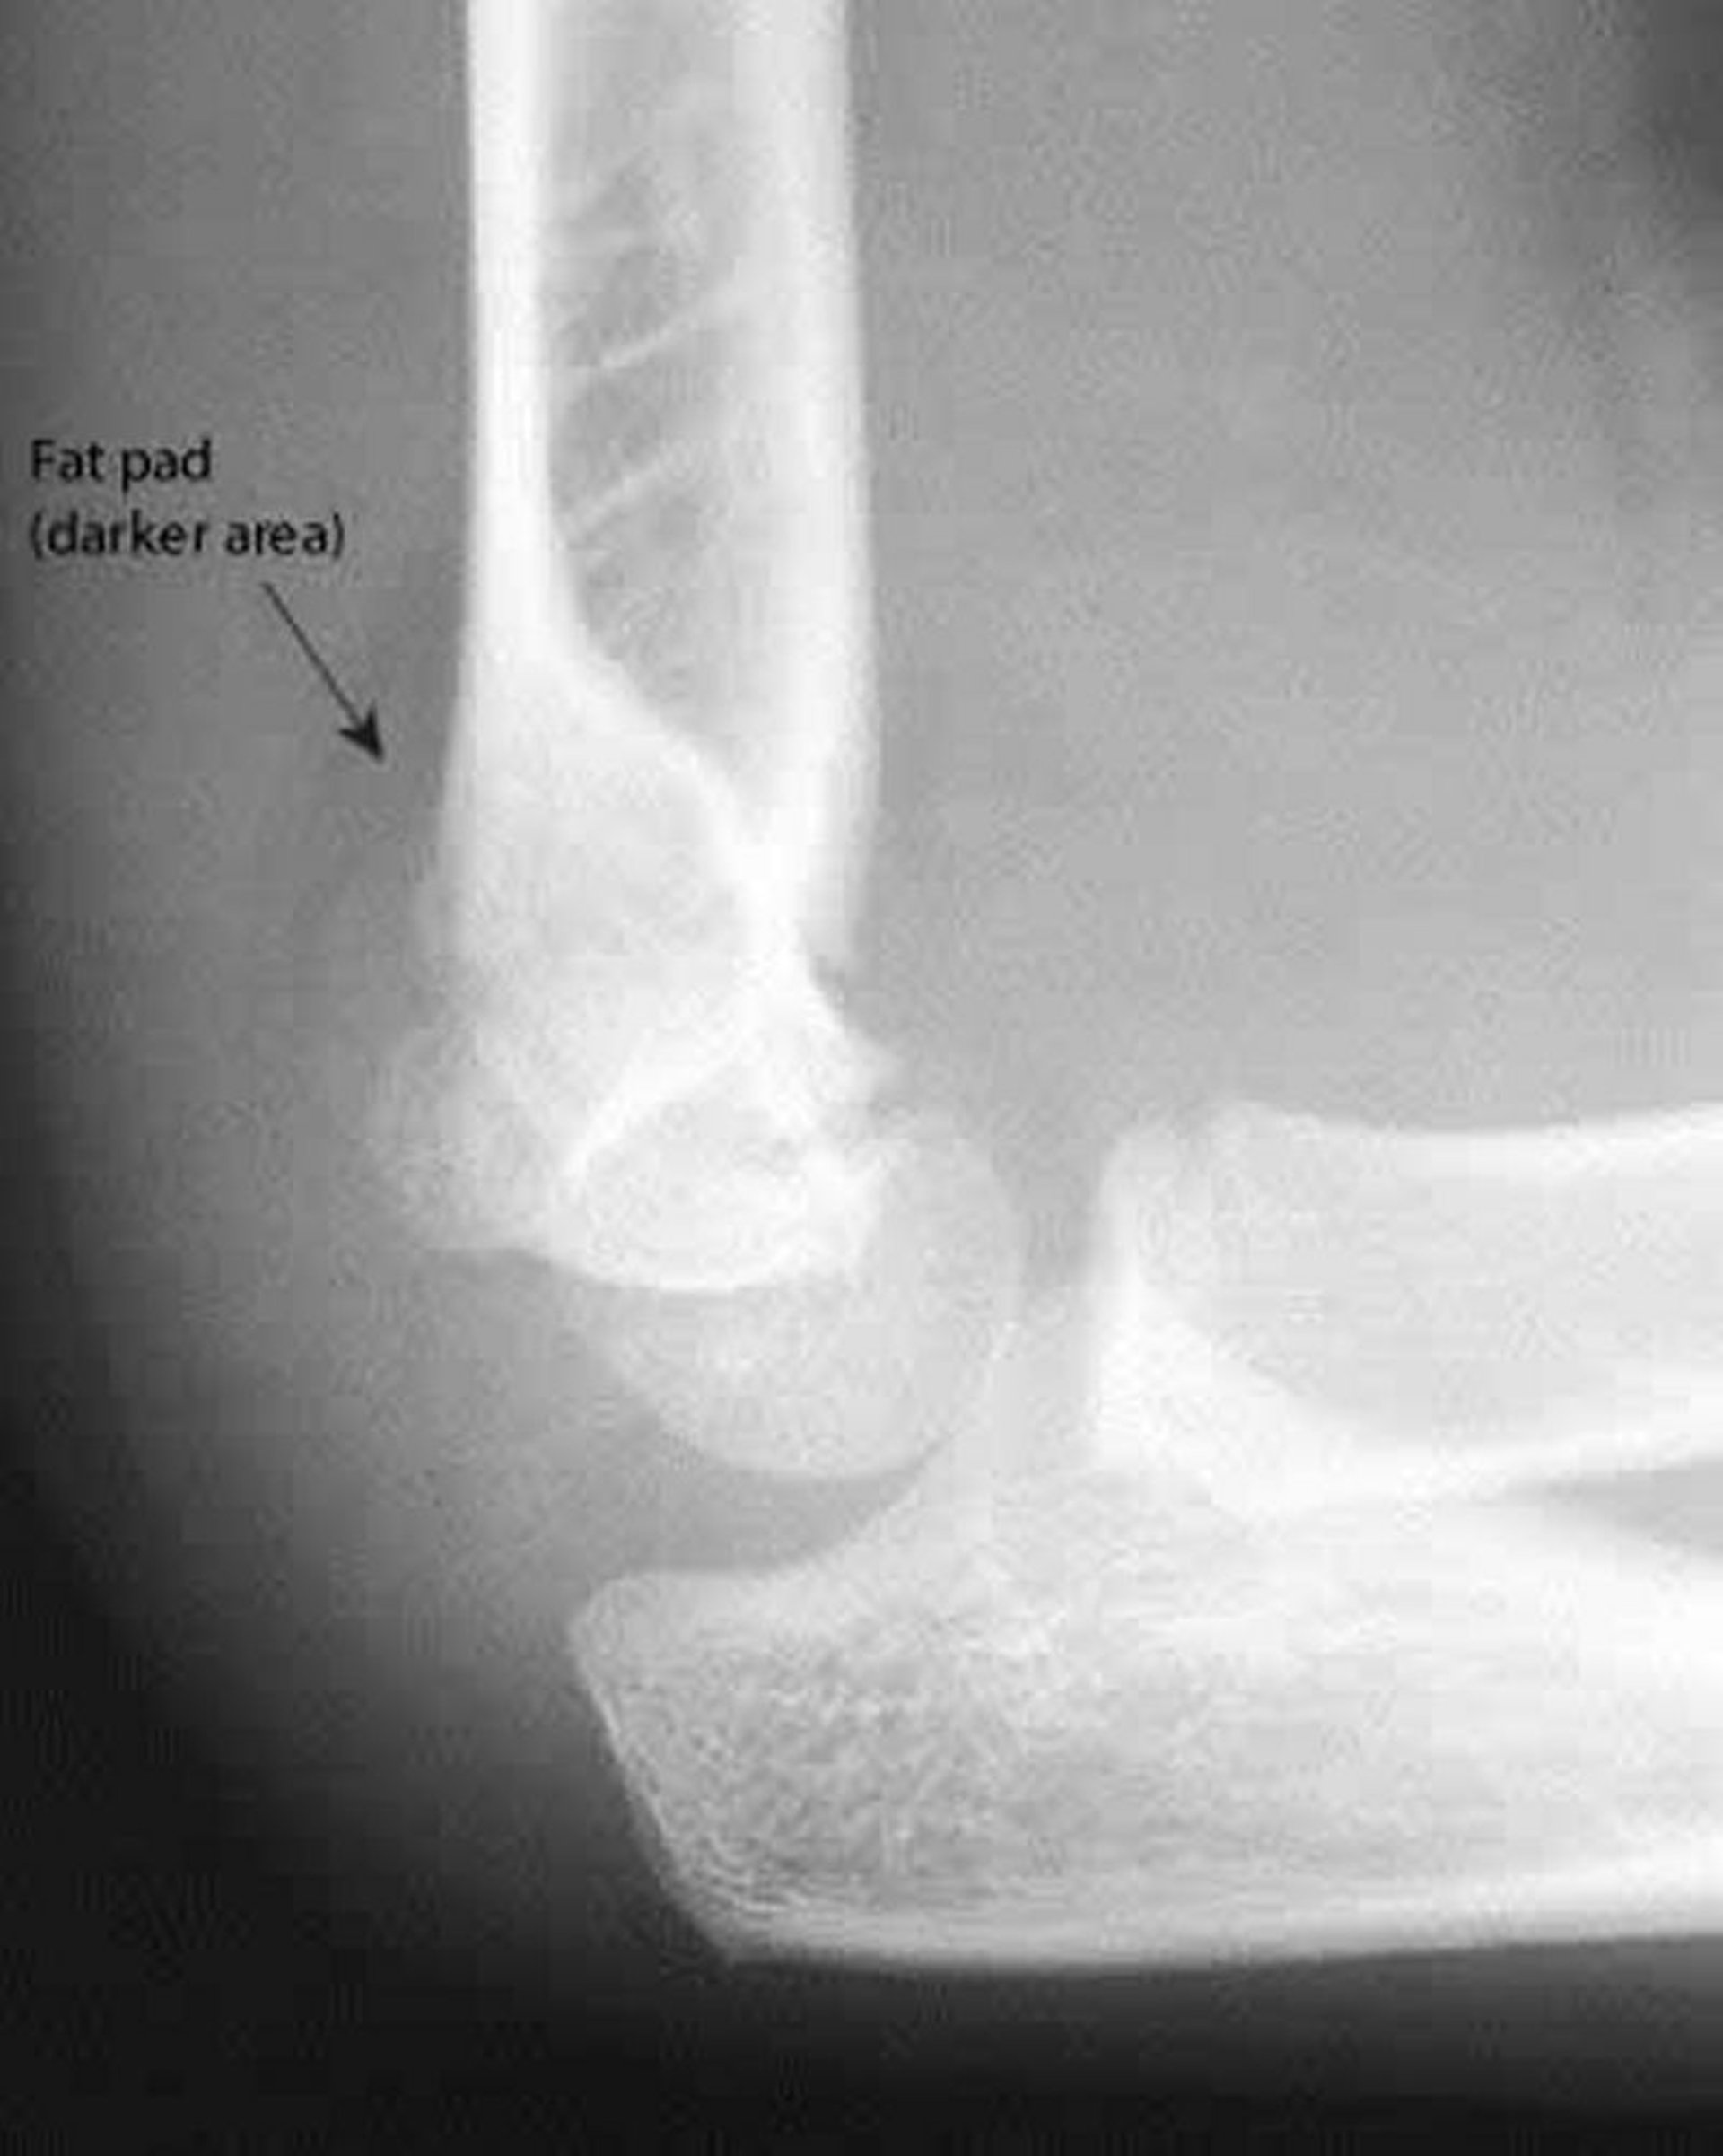

Una almohadilla grasa posterior es siempre anormal. También en esta radiografía, la línea humeral anterior no atraviesa el punto medio del capítulo humeral.